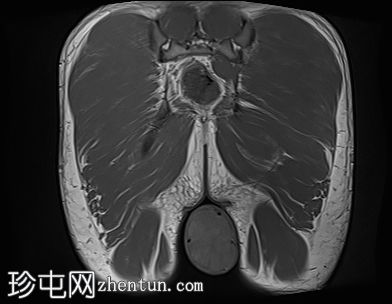

轴位

T1加权像

4.jpg

阴囊内睾丸增大,T1加权像上可见分叶状软组织病变,呈中高信号,T2加权像上呈低信号。

轻度双侧鞘膜积液。

本病例表现为双侧睾丸肿胀,影像学特征符合睾丸肾上腺残余肿瘤的典型表现,即T1加权像上呈双侧中高信号,T2加权像上呈低信号。